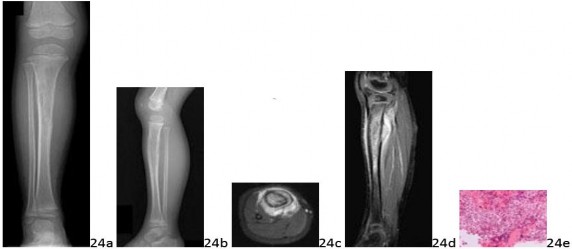

Question 24 A 4-year-old boy has a 3-month history of limping and pain in the right tibia. According to his parents, he has frequent night pain. There is no history of weight loss, fevers, or night sweats. Examination reveals that the left tibia is moderately tender to palpation. There is no palpable mass or lymphadenopathy. Radiographs, MRI scans, and biopsy specimens are seen in Figures 24a through 24f. What is the fusion protein frequently associated with this disorder?

Question 24 A 4-year-old boy has a 3-month history of limping and pain in the right tibia. According to his parents, he has frequent night pain. There is no history of weight loss, fevers, or night sweats. Examination reveals that the left tibia is moderately tender to palpation. There is no palpable mass or lymphadenopathy. Radiographs, MRI scans, and biopsy specimens are seen in Figures 24a through 24f. What is the fusion protein frequently associated with this disorder?

1. ## SYT-SSX

2. ## ASPL-TFE3

3. ## EWS-ATF1

4. ## EWS-FLI1

5. ## TLS-CHOP

DISCUSSION: The permeative changes and "onion skin" periosteal reaction with no observable matrix production on radiographs are suspicious for Ewing's sarcoma. The cells are small, round, and monotonous on low power and have large hyperchromatic nuclei and indistinct cytoplasmic borders on high power, supporting the diagnosis of Ewing's sarcoma. Molecular analysis confirmed the EWS-FLI1 mutation. The radiographic differential diagnosis includes: osteomyelitis, Langerhans cell histiocytosis, and lymphoma. EWS-ATF1 is associated with clear cell sarcoma, while ASPL-TFE3 is associated with alveolar soft part sarcoma. SYT-SSX and TLS-CHOP are associated with synovial sarcoma and liposarcoma, respectively. The Preferred Response to Question # 24 is 4.